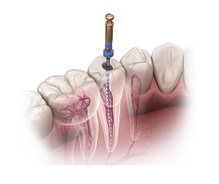

Precision and Accuracy

Digital technologies allow for extremely precise measurements and fabrication of dental restorations. This precision leads to a better fit, which can improve the longevity of the restoration and the overall health of the surrounding teeth and gums.

Cone beam CT imaging offers incredibly detailed 3D scans for improved diagnostic abilities and surgical planning.

From digital smile design to guided implant surgery, digital dentistry empowers your team to work with unprecedented accuracy and efficiency.